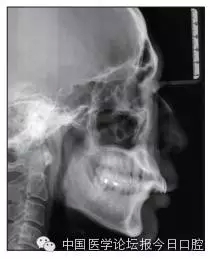

全口曲面體層片(圖3)顯示,患者全牙列牙槽骨吸收;根尖片(圖4)示11近中牙槽骨角形吸收已達(dá)根尖1/3,21牙槽骨嵴頂吸收至根1/2,23牙槽骨近中骨板角形吸收至根1/2。磨牙區(qū)骨嵴頂吸收3mm。治療前頭顱側(cè)位片見圖3,治療前ODS模型見圖5。

圖3 治療前頭顱側(cè)位片及曲面體層片